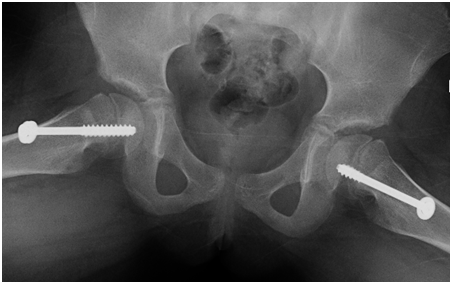

She has tiredness and fatigue and non-specific symptoms. She was treated with thyroxin and her thyroid functions test normalized in 2months time. After her improvement of thyroid functions test she developed limping and pain in her left leg which get worse with activity. We tested her bone profile and we found vitamin D deficiency so she received treatment for that. But in spite of improvement of the vitamin d deficiency and thyroid disease she continue to have the limping and pain in her leg so we referred her to orthopedics. The orthopedic did for her pelvic AP x-ray and found Bilateral symmetrical slipped capital proximal femoral epiphyses are noted with metaphyseal sclerosis and irregularity. The proximal femoral epiphyses are of normal density and contour Unremarkable acceptable in both sides. So she was treated surgically and cannulated screw fixation was done in both hip joints. After that the patient improved regarding limping and pain and without complaints.

In this case we present that after treatment of the sever hypothyroidism the symptoms of masked SCFE appears indicating that evaluations of thyroid function test is strongly recommended in cases of SCFE (Figures 1‒3).

Figure 3 Slipped capital femoral epiphysis in 10years old girl.